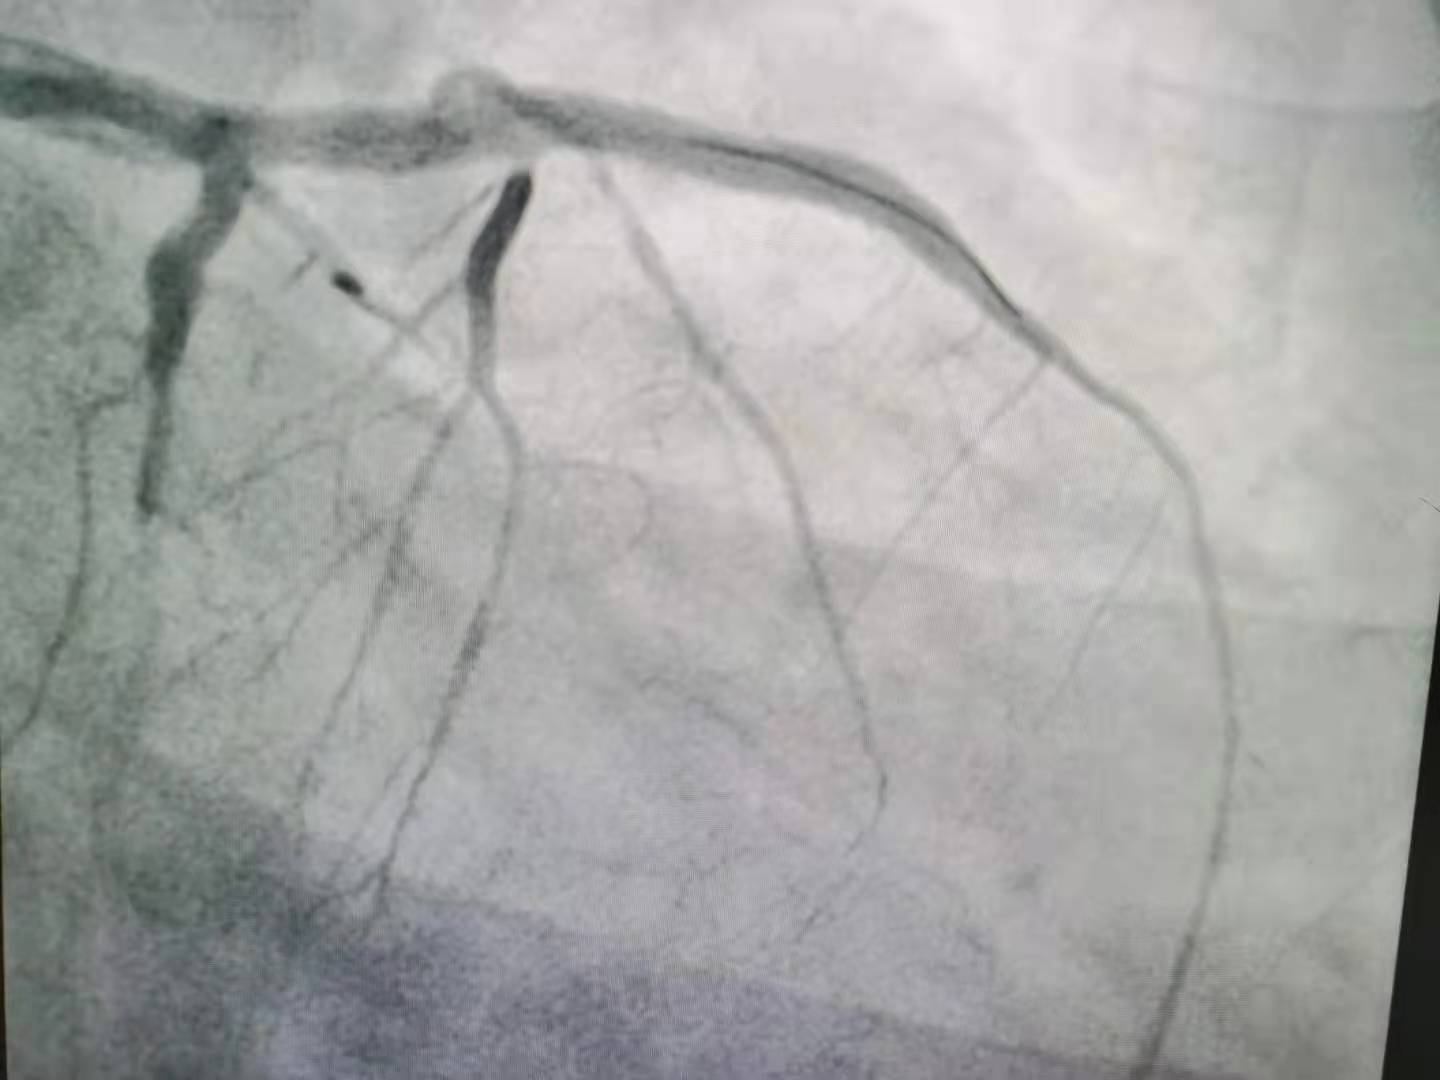

经过手术,血管成功开通。上:血管开通前,下:血管开通后。

经过抢救,做了支架植入,小杨才转危为安。清醒后的小杨不能理解,自己才二十多岁,怎么就心梗了?